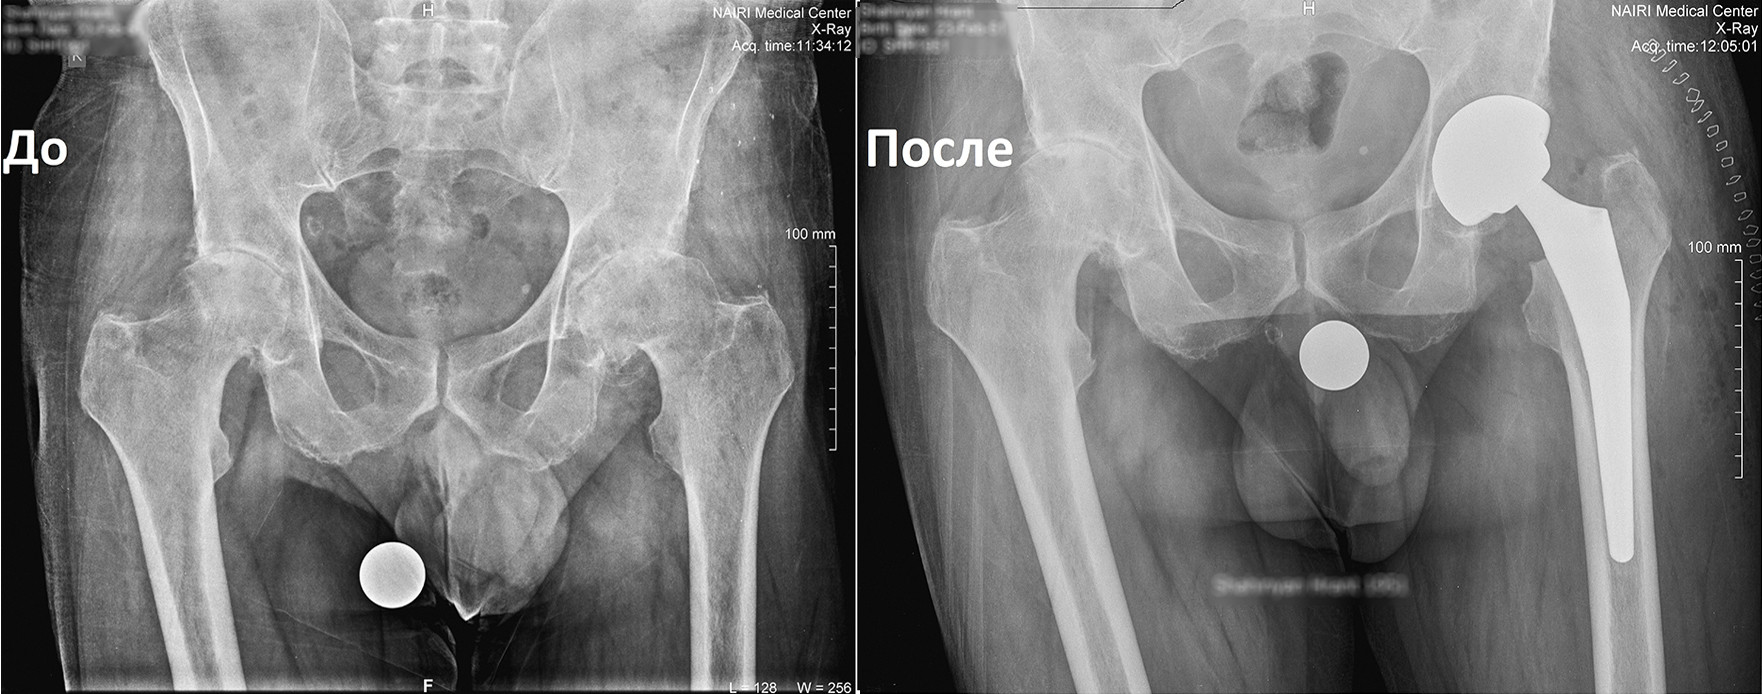

Որոշում կայացվեց իրականացնել փուլային երկու վիրահատություն: Առաջինը վիրահատվեց ձախ ոտքը, քանի որ այդ վերջույթում ձևախախտումն առավել արտահայտված էր:

Երկու ամիս անց, երբ պացիենտը սկսեց քայլել առանց հենակների, վիրահատվեց նաև աջ ոտքը:

Երկրորդ վիրահատությունից 6 շաբաթ անց պացիենտը ցավեր չունի և քայլում է առանց հենակների, ապրում լիարժեք կյանքով: